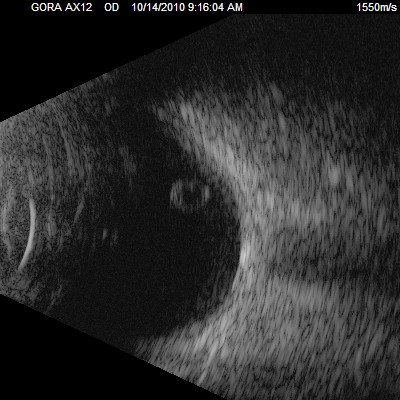

Przedstawiane obrazy ultrasonograficzne® są oryginalne i pochodzą z mojej praktyki lekarskiej